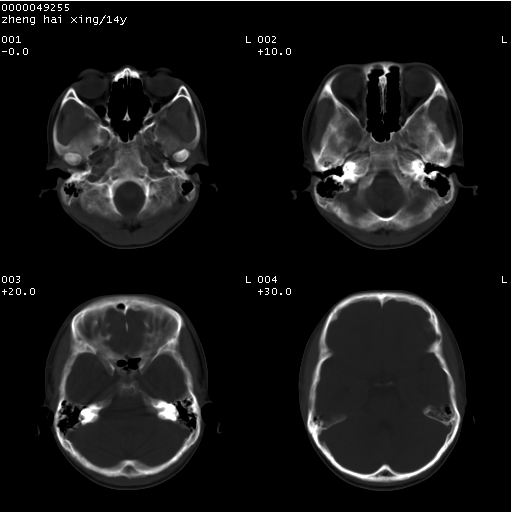

患儿 男,14岁。头部外伤1小时。pe:发育正常,营养良好,生命体征稳定,未见明显阳性体征。

临床诊断:ⅰ级脑外伤。

颅脑ct轴位平扫(层厚、层距均为10mm),图像如下:

(患儿平素健康,双眼视力正常,无神经系统及内分泌系统症状及体征)